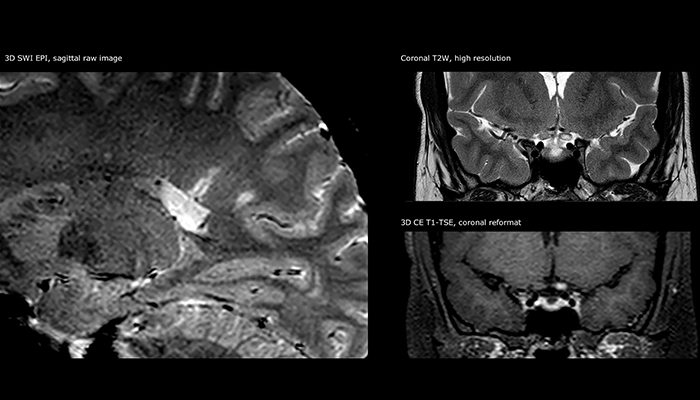

For MS imaging in the brain, Dr. Savatovsky uses 3D FLAIR as the basic sequence to visualize the lesions and assess the situation and lesion load. “We count the lesions in each location to determine if the criteria of the disease are fulfilled. We use a T2-weighted sequence because our neurologists are used to it. We compare the lesion load on FLAIR with a 3D T1 post-contrast sequence to help us determine whether lesions are old or new. We typically administer the contrast before the patient enters the machine because it shortens the examination time and allows to visualize active lesions that tend to be more visible after several minutes. When a differential diagnosis is difficult, we add sequences such as susceptibility imaging, because some focal MS lesions have a small vein in the center[3].”

“The biggest challenges are properly characterizing the lesion and giving the surgeon all the information needed, such as the location of vessels and functional areas. Sometimes a very comprehensive exam is necessary, such as when a mass has been discovered at another hospital after which the patient is referred to us. We then do both lesion characterization and preoperative imaging in one exam, so both morphologic and functional assessment. For morphologic assessment we will use pre- and post-contrast T1-weighted imaging, FLAIR to assess infiltration, and diffusion. For functional characterization we will perform perfusion, spectroscopy, and susceptibility weighted imaging to look for micro vessels or micro hemorrhage inside the lesion[4]. For preoperative imaging we perform specific morphologic imaging that is compatible with the navigation system; depending on the location of the tumor, we would do fMRI or DTI.”